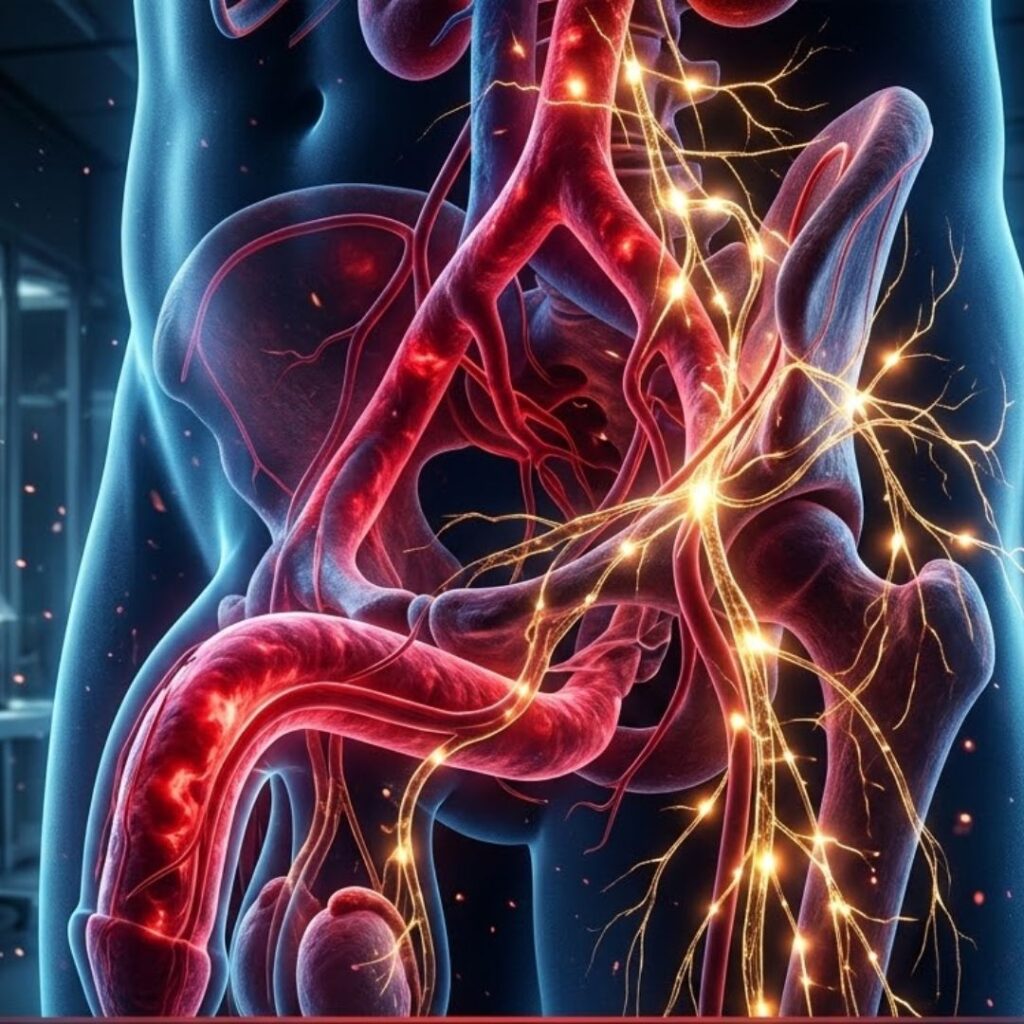

The Cavernous Nerves — The Wiring Behind Every Erection

Running from the base of your spinal cord, through your pelvic region, and into the erectile tissue of the penis, there is a set of nerve fibres called the cavernous nerves.

These nerves are part of the autonomic nervous system.

They operate entirely below the level of conscious control.

You have never had to think about them. They simply do their job.

Here is what that job is:

When your brain registers arousal — a thought, a touch, a visual stimulus, an emotional connection with someone you love — it generates an electrical signal.

That signal travels down through the spinal cord, passes through a nerve relay point in the pelvis called the pelvic plexus, and then travels along the cavernous nerves directly into the smooth muscle tissue lining the corpora cavernosa — the two chambers inside the penis that fill with blood during erection.

The signal instructs that smooth muscle to relax.

When the muscle relaxes, the internal blood vessels dilate. Blood rushes into the chambers. The penis becomes erect.

That is the entire system. Brain generates signal. Cavernous nerves carry it. Smooth muscle relaxes. Blood fills the chambers. Erection occurs.

Elegant. Automatic. It has been working without any conscious effort on your part since adolescence.

Until, gradually, it stopped.

This is what happens in the cavernous nerve network of the majority of men who develop progressive erectile dysfunction after the age of 50:

The protective myelin sheath that insulates the cavernous nerve fibres begins to degrade.

This process — called progressive cavernous nerve demyelination — is silent, cumulative, and slow.

Most men don’t notice it until the damage has already become significant, because the nervous system compensates for minor degradation in ways that aren’t obviously detectable.

The brain continues to generate the arousal signal perfectly.

The desire is completely intact.

But the signal travels along a compromised nerve pathway — losing strength, losing speed, losing precision with every millimetre of degraded myelin it passes through — and arrives at the smooth muscle tissue too weakened to trigger the full relaxation response.

The blood doesn’t rush in the way it once did.

The erection is partial. Or slow. Or it starts and then fades before it’s fully there.

It is not that your body does not want to respond. It is that the message is no longer getting through cleanly. And every month that passes without addressing the underlying nerve degradation, a little more of the signal is lost in transit.